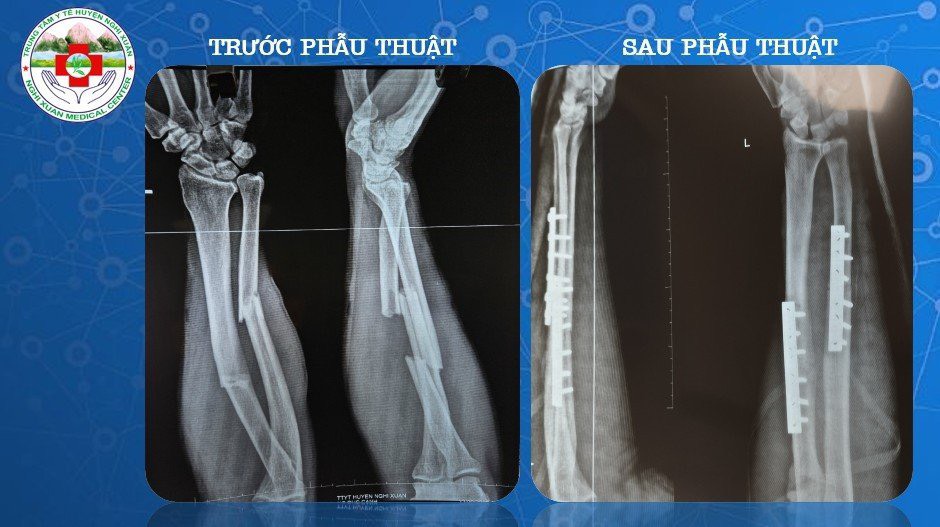

Hình ảnh xương trước và sau phẫu thuật

Qua thăm khám lâm sàng kết hợp với các phương pháp chẩn đoán hình ảnh, bệnh nhân được chẩn đoán: Gãy phức tạp 1/3 giữa 2 xương cẳng tay trái di lệch/ Gãy xương sườn. Các bác sĩ khoa Ngoại Tổng hợp đã nhanh chóng cấp cứu tích cực cho bệnh nhân cũng như hồi sức dự phòng chống sốc chấn thương, tiêm truyền thuốc giảm đau, hội chẩn và hoàn thiện xét nghiệm để tiến hành phẫu thuật kết hợp xương bệnh nhân một cách nhanh nhất. Sau 1 tiếng, ê kíp gây mê cùng các bác sĩ, phẫu thuật viên đã phẫu thuật thành công cho bệnh nhân. Hiện sức khỏe của bệnh nhân đã ổn định và được xuất viện.

Theo BS CKI Lê Viết Hùng – Giám đốc Bệnh viện- Nguyên Trưởng khoa Ngoại của Trung Tâm Y Tế cho biết: “Khoa Ngoại Tổng hợp hiện đang triển khai phương pháp phẫu thuật kết hợp xương bằng phương pháp sử dụng nẹp vít để cố định xương thẳng trục. Đây là phương pháp phòng ngừa biến chứng cho bệnh nhân gãy xương với nhiều ưu điểm như: Cố định vững chắc, bộc lộ chính xác vị trí ổ gãy xương, giảm số ngày nằm viện, điều kiện tập phục hồi chức năng sớm, bệnh nhân sớm trở lại sinh hoạt bình thường”. Được biết, các bác sĩ Khoa Ngoại Tổng hợp đã thực hiện rất nhiều ca phẫu thuật kết hợp xương hiệu quả bao gồm các phẫu thuật xương khớp như kết hợp xương trong gãy xương đòn, xương cánh tay, xương cẳng tay, xương đùi…Đó là tiền đề để các cán bộ, nhân viên y tế trong khoa không ngừng học tập nâng cao trình độ chuyên môn áp dụng vào trong công tác khám chữa bệnh cho nhân dân; giúp giảm tải cho tuyến trên và giảm chi phí điều trị cho bệnh nhân.